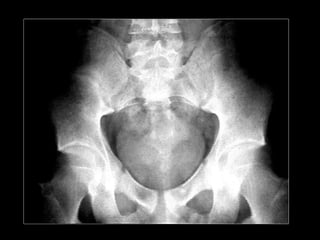

Secondary HPT. Radiograph of the pelvis and hips showing diffuse osteosclerosis.

Secondary HPT. Radiographof the pelvis and hips showing diffuse osteosclerosis.